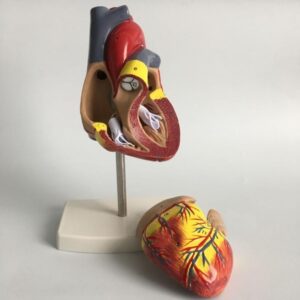

1: 1 Anatomisches Modell des menschlichen Herzens Kardiologie Lehrmodell der Herzanatomie mit Nummernmarkierung

CHF 41.64 -